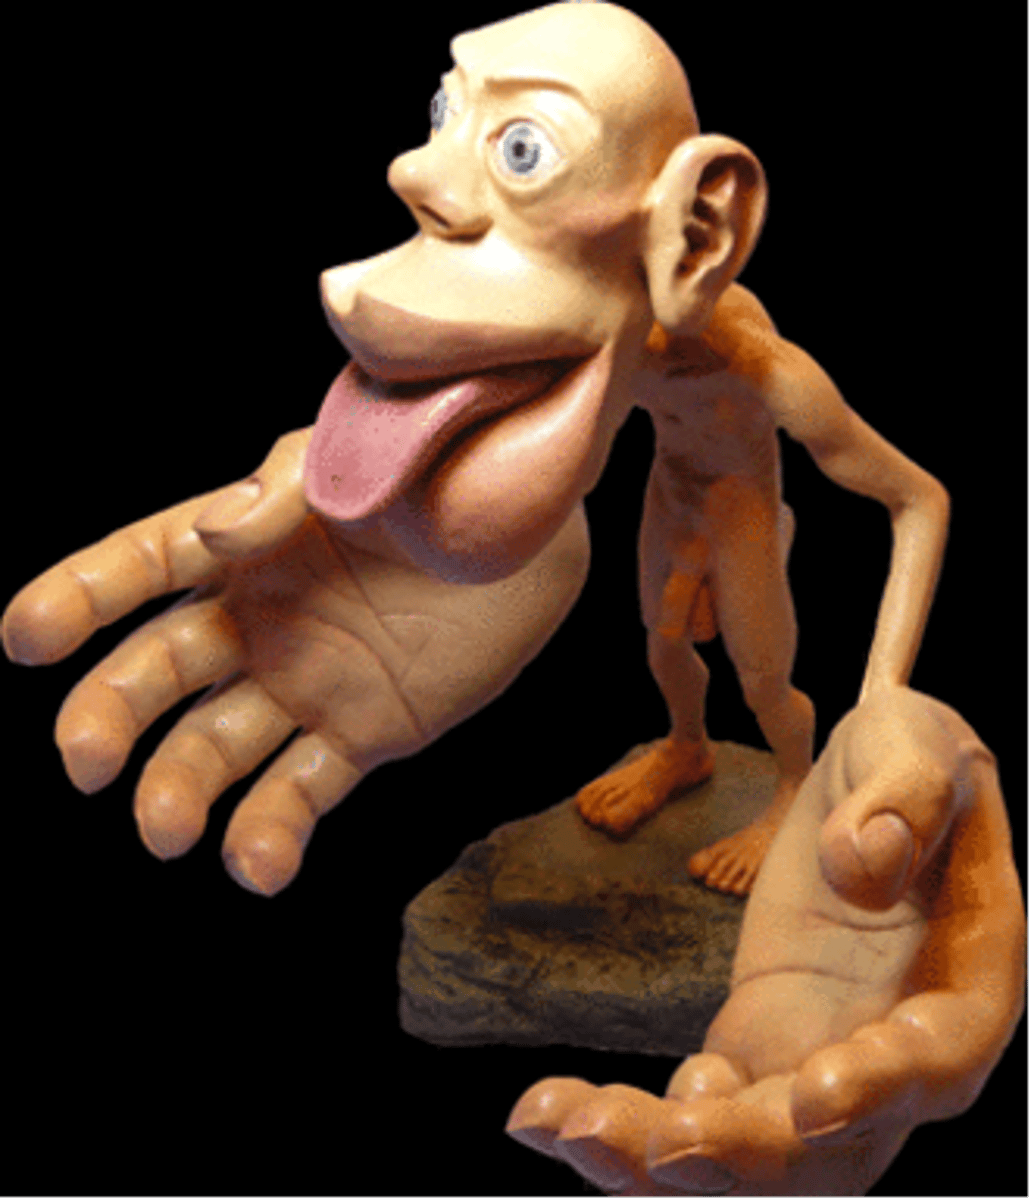

what term refers to how a specific part of the body is associated with a distinct location in the CNS?

somatotropy

(t/f) the homunculus is a proportional representation of the human body superimposed on the primary motor and primary somatosensory areas of cortex. areas of greater sensory sensitivity or capacity for finer, discrete movement have a smaller relative degree of cortical representation.

false; areas of greater sensory sensitivity or capacity for finer, discrete movement have a greater relative degree of cortical representation